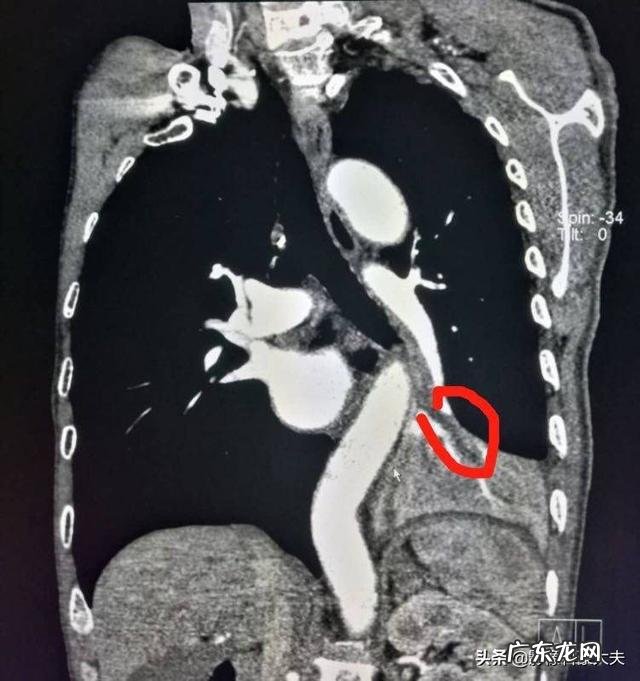

这位老爷子62岁,抽烟几十年,反复咳嗽住院,发现左下叶肺不张,开始以为得肺癌了,很害怕!

增强CT发现支气管内充满了低密度的痰栓,经过雾化(稀释痰液)和消炎zhi疗,一周出院了 。